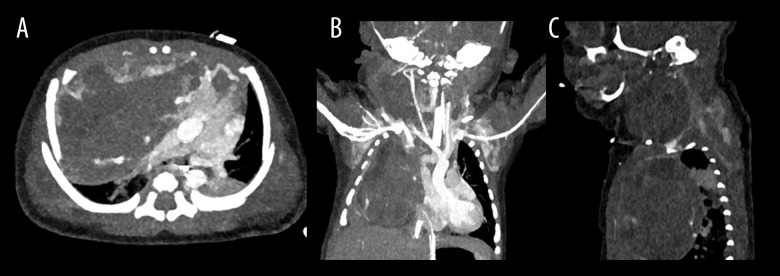

背景:在潜在的产后气道阻塞的情况下,宫内气管治疗(EXIT)是一项复杂的围产期手术。它需要一个经验丰富的多学科团队和基于胎儿成像的细致的手术计划。本报告描述了使用出口到气道的大宫颈畸胎瘤延伸到纵隔。病例报告:在妊娠35周时,一名29岁的女性因羊水过多来到我们的胎儿护理中心。胎儿随后被诊断为一个大的宫颈肿块延伸到纵隔。妊娠36周时进行出口至气道手术。在获得产后成像时,新生儿仍插管。在出生第3天,通过宫颈和纵隔联合入路切除畸胎瘤。病理证实为成熟畸胎瘤。新生儿的住院过程因吸入和喂养而变得复杂,需要胃造口管,她在出生第40天出院。结论:虽然宫颈畸胎瘤是EXIT手术的一个明确的适应症,但该病例因其妊娠晚期晚期的诊断和罕见的肿块延伸到纵隔,需要双重手术入路。它强调了在反复发生的晚期羊水过多的情况下维持广泛的鉴别诊断的重要性,并证明了多学科计划在预期气道损害时优化结果的关键作用。本病例提供了越来越多的证据,支持在复杂的颈纵隔肿块中扩大出口到气道的应用。

BACKGROUND Ex-utero intrapartum treatment (EXIT)-to-airway is a complex perinatal procedure performed in the case of potential postnatal airway obstruction. It requires an experienced multidisciplinary team and meticulous surgical planning based on fetal imaging. This report describes the use of EXIT-to-airway for a large cervical teratoma with extension into the mediastinum. CASE REPORT At 35 weeks' gestation, a 29-year-old woman presented to our fetal care center with significant polyhydramnios. The fetus was subsequently diagnosed with a large cervical mass extending into the mediastinum. An EXIT-to-airway procedure was performed at 36 weeks' gestation. The neonate remained intubated while postnatal imaging was obtained. At day of life 3, resection of the teratoma was performed via a combined cervical and mediastinal approach. Pathology confirmed a mature teratoma. The neonate's hospital course was complicated by aspiration with feeding, requiring a gastrostomy tube, and she was discharged on day of life 40. CONCLUSIONS While cervical teratoma is a well-established indication for the EXIT procedure, this case is notable for its late third-trimester diagnosis and the rare extension of the mass into the mediastinum, which necessitated a dual surgical approach. It highlights the importance of maintaining a broad differential diagnosis in the setting of recurrent third-trimester polyhydramnios and demonstrates the critical role of multidisciplinary planning in optimizing outcomes when airway compromise is anticipated. This case contributes to the growing body of evidence supporting the expanded utility of EXIT-to-airway for complex cervicomediastinal masses.